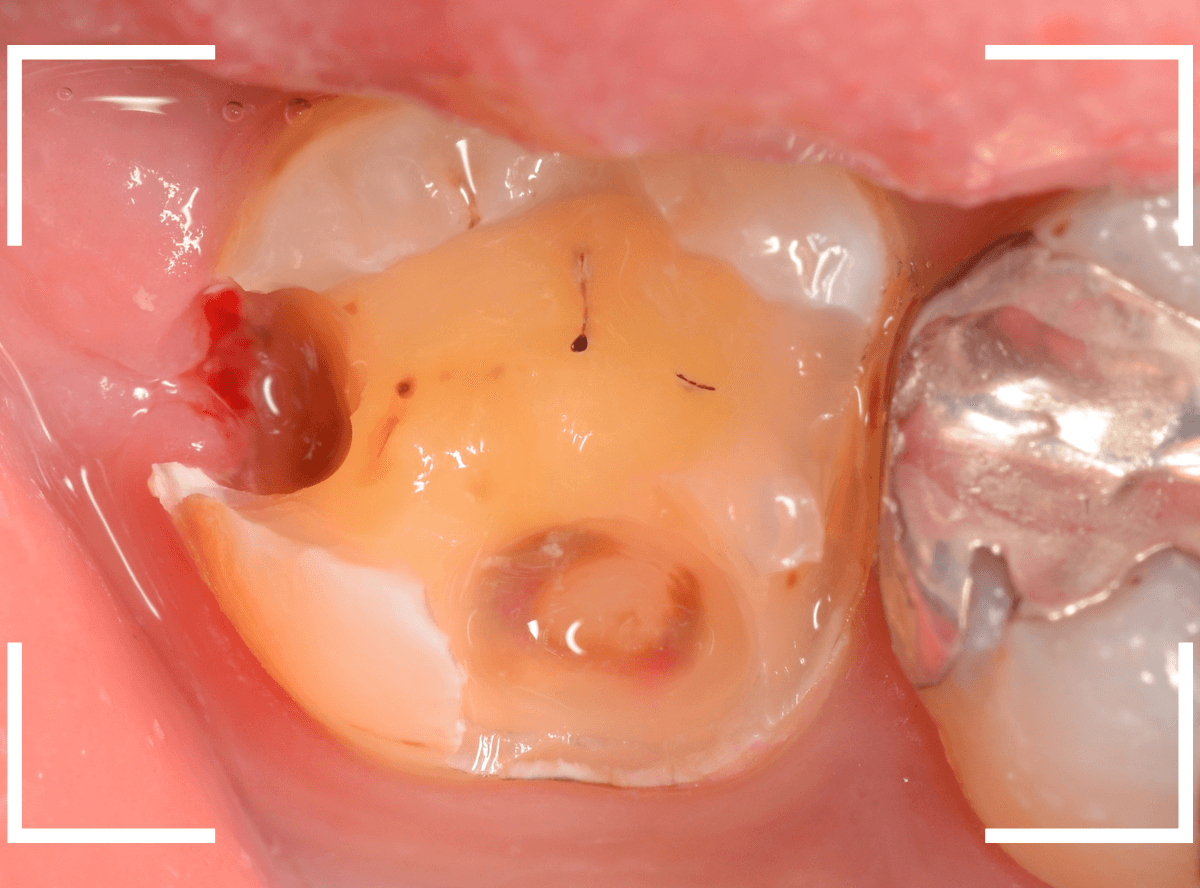

Case.16 レントゲンにはっきり写らないレジンの中の虫歯を削って調べる

「たまに下の歯の奥歯が痛む」という症状で来院された患者さんの例です。

特にはっきりと虫歯らしい箇所はなく、打診(歯を叩いた症状の違いで、痛みの原因の歯を調べる)でも特に反応はありませんでした。

このように不定期な痛みの原因は特定しづらい事が多いです。

さて、レントゲン写真で確認すると、上の写真の歯のレジンをつめてある下が少し虫歯っぽい写り方をしています。

あとはレジンを外して調べてみるしかないのですが、レントゲンではっきりした写り方ではないので、虫歯が見つからない可能性も患者さんに説明しましたが、治療をご希望されたので、レジンを外して調べる事になりました。

レジンを削って中を調べてみると、レジンの中は思ったよりもスカスカの状態でした。

これでは、なにか症状を感じてもおかしくありません。

レジンの下には神経を保護するためのセメントがしいてありましたが、その下も茶色く着色しており、虫歯になっていそうです(着色してるから虫歯かというと、そうとも限りません)。

セメントを慎重に除去していきます。

レントゲン写真から、前の先生が治療をした時点で神経に近いところまで削っているのはわかります。

そのために、レジンの下にセメントをしいて、しみるなどの神経症状を緩和させていたのです。

怖いですが、もう少しセメントを外して調べます。

ほぼほぼ、つめてあったレジンとセメントを除去しました。

着色している部分は、器具で触るとやわらかくボソボソしており、虫歯と判断して間違いありません。

慎重にすべての虫歯を除去しました。

想像以上に虫歯は深く広く、神経の薄皮一枚というところまで進行していました。

この状況でお薬をしっかりつめなおして、症状をしばらく経過観察します。

おそらく、改善してくれると思うのですが。。。